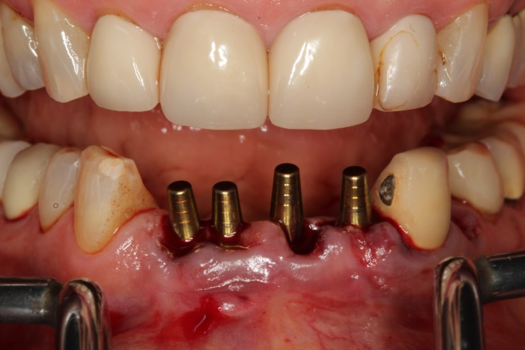

The next case follows the digital protocol for fully guided surgery and prosthetics. A CBCT radiograph, digital impression, and digital photography were the cornerstones to the success of this case. The 3D data set was electronically delivered to the dental laboratory. The data were merged and the process to develop the plan was initiated. The use of CBCT was essential in this case, particularly due to minimal space for placement of individual implants and single-unit crowns. The patient's chief concern was that she wanted to have single-unit crowns instead of fixed crown-and-bridge restorations because she was worried that she would someday find herself in an assisted-living facility; if that were to happen, she wondered, who would help floss under her bridge work? Her decision was to have single implants with individual crowns. CBCT technology is much more accurate in evaluating space maintenance and management.10 Periapicals in the past were rather close for calculating spacing; however, the CBCT identifies the buccal-lingual dimensions as well as the mesial-distal measurements. On review of the completed proposals for implant placement and provisionals, it was determined that there was sufficient spacing for implant placement to allow appropriate emergence profiles for the provisionals and then eventually the final single-unit cemented crowns. The proposal was accepted, and a 3D-printed surgical stent was fabricated, along with the PMMA provisionals (Figure 29 through Figure 35).

On the day of surgery, the plan was to extract teeth Nos. 21, 23, 24, 25, and 26, place 3.0 x 13-mm implants in the anterior region due to limited spacing, and place a 4.1 x 10-mm implant in the No. 21 extraction site. Before the extractions were performed, the No. 23 pontic was sectioned from the existing 2-unit cantilevered bridge utilizing ceramic and metal high speed rotary cutting burs ZR 6881 and H34L (Komet-USA), respectively. After removal of the pontic and extractions, the surgical guide was verified to be seating positively (Figure 36 through Figure 38). Surgical guide protocol was followed, and all implants were successfully placed and torqued to a value of greater than 35 Ncm (Figure 39 and Figure 40). All implants were placed without flapping, with the exception of No. 23. The flap was elevated to reposition lingual keratinized tissue facially for enhanced esthetic tissue profile. The implants were then prepared with a high-speed carbide bur (Komet-USA) with copious amounts of water (Figure 41 and Figure 42). The one-piece 3.0-mm diameter implant served the needs of the patient's spacing requirements. Inter-occlusal space requirements and path of draw were verified. The PMMA provisionals were air abraded and relined with crown-and-bridge material (Figure 43 through Figure 45).

Fig 36. Anterior central view.

Figure 36

Fig 37. Pontic removal of No. 23 and teeth extractions.

Figure 37

Fig 38. Periodontal casualties.

Figure 38

Fig 39. Surgical guide in place.

Figure 39

Fig 40. 3 x 13-mm implants.

Figure 40

Fig 41. Abutment preparation.

Figure 41

Fig 42. Occlusal view of prepared implants.